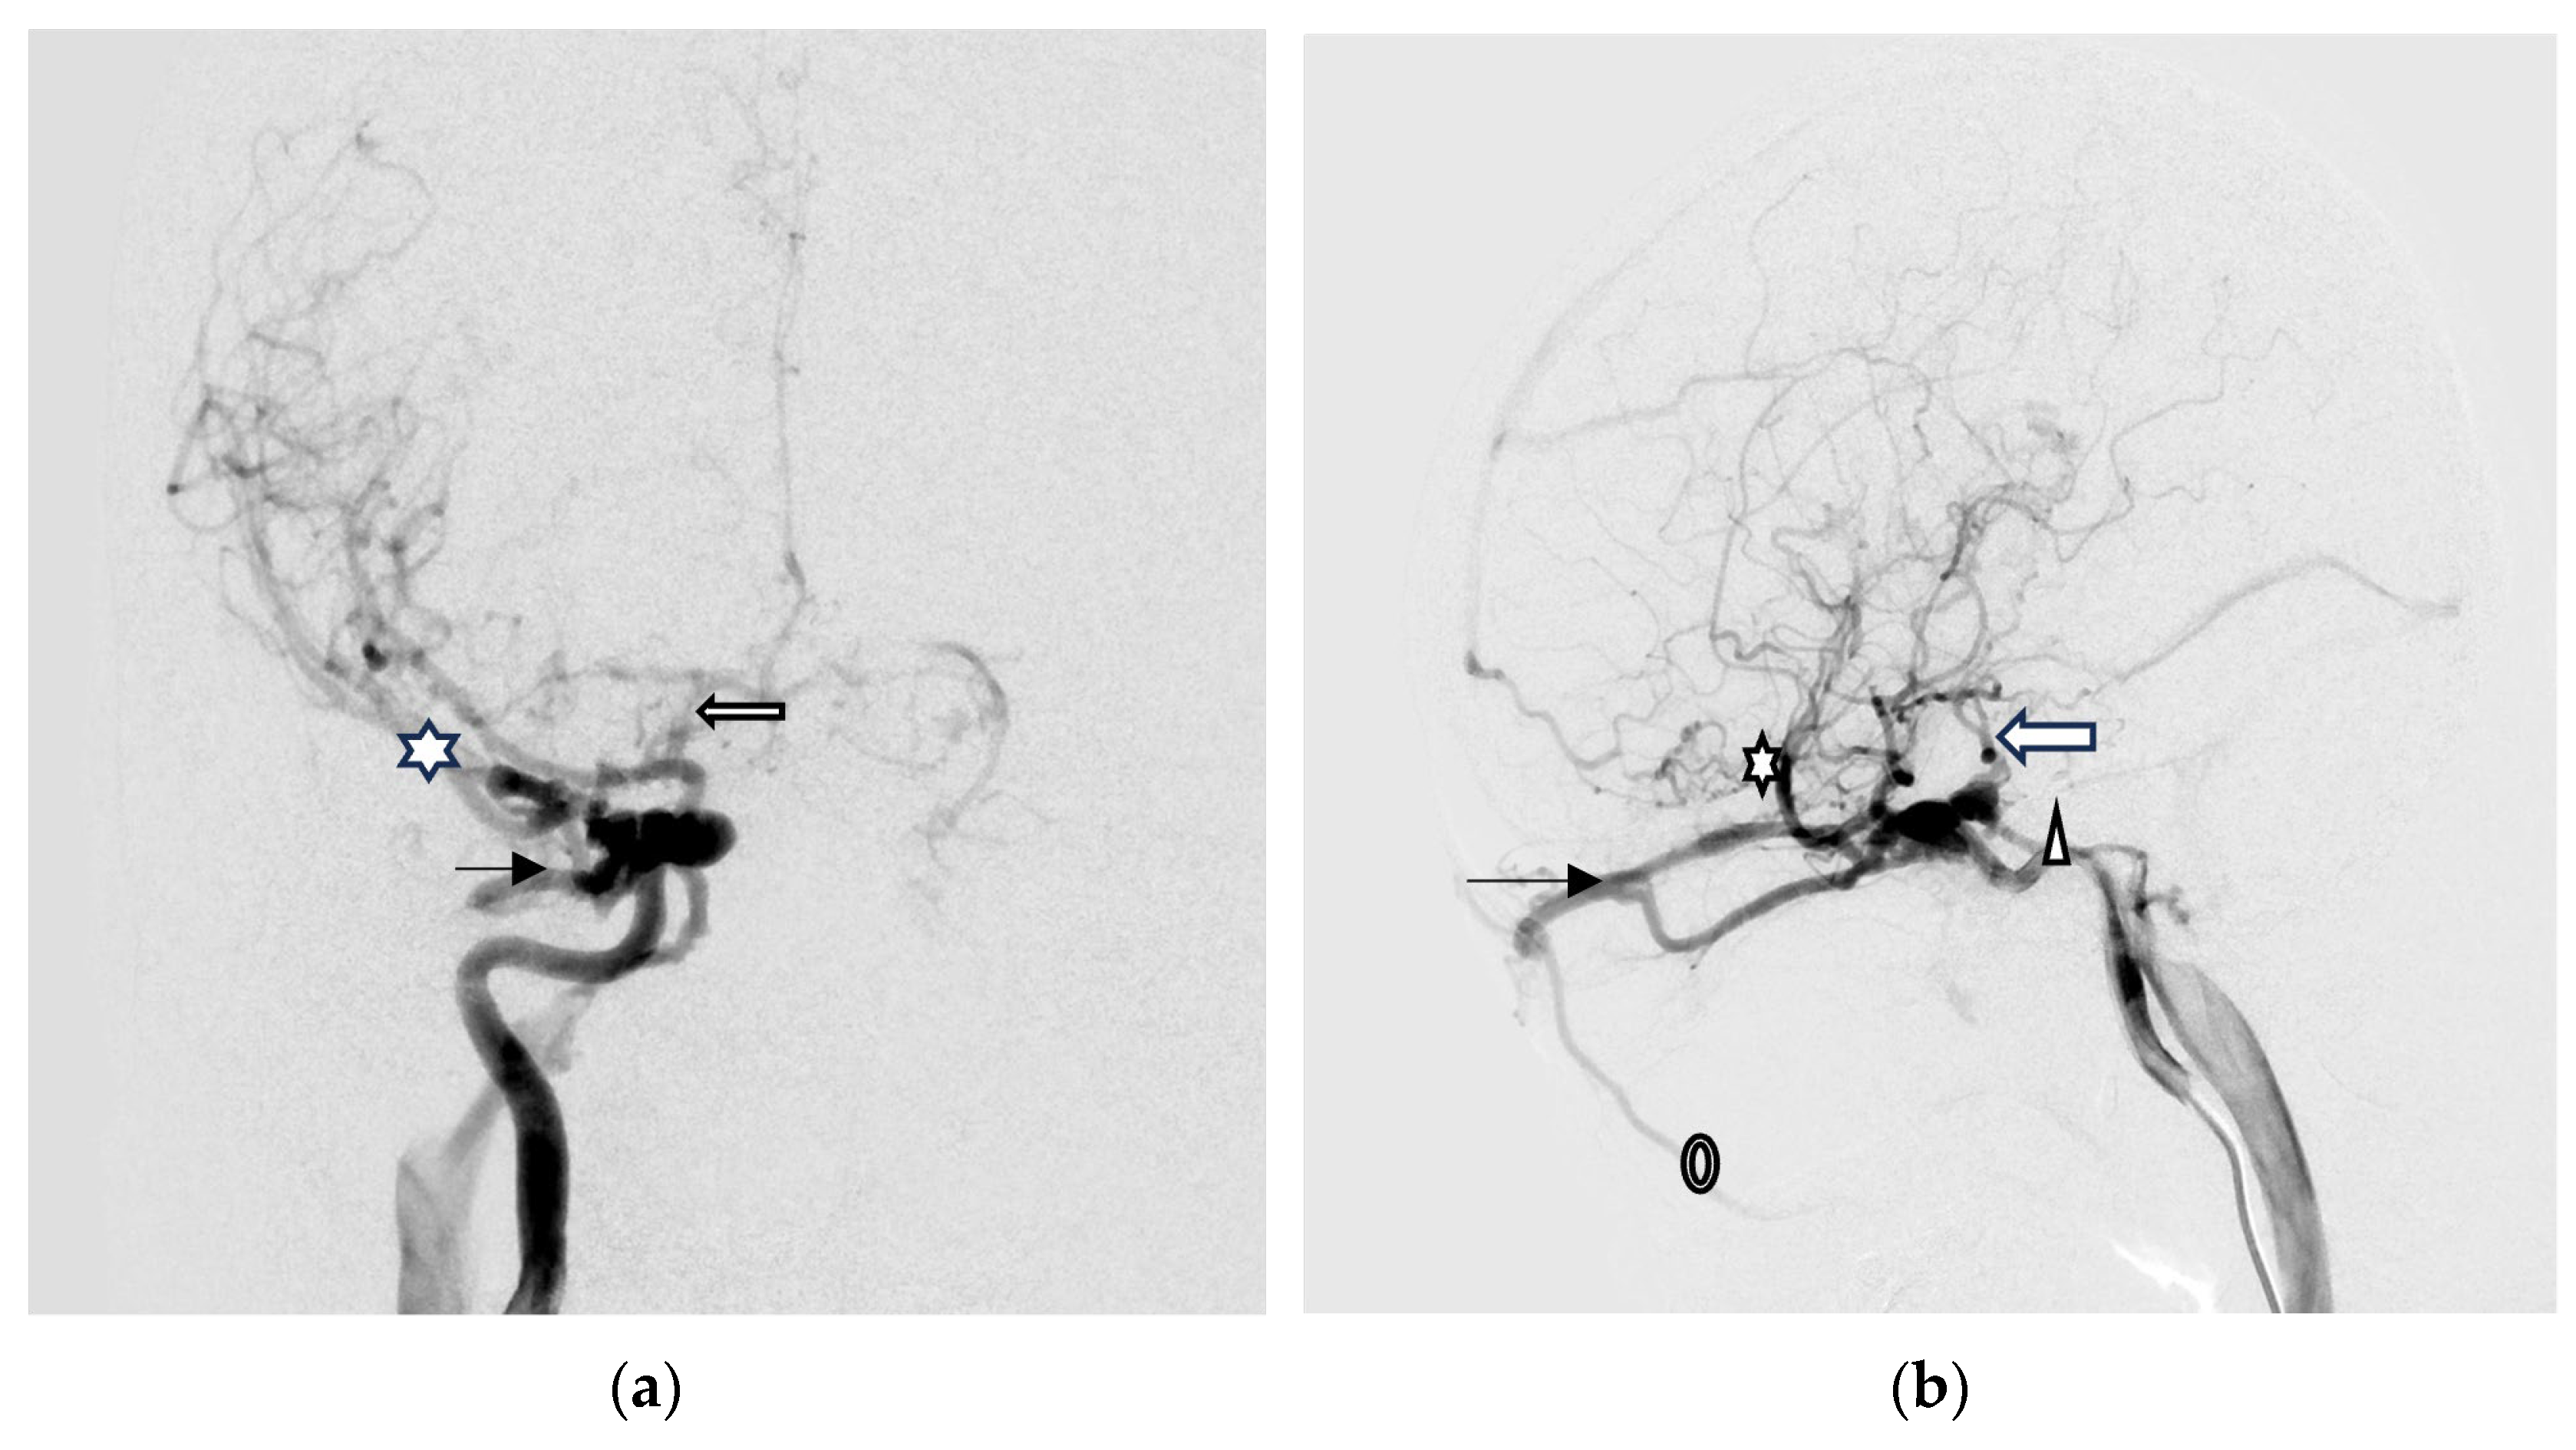

Digital subtraction angiography (DSA) was performed to confirm a direct type high-flow CCF of the right-side ICA with reflux flow into the right SOV and inferior ophthalmic vein (IOV), the right superficial middle cerebral vein (SMCV), the right superior petrosal sinus (SPS), and the right inferior petrosal sinus (IPS). Right facial vein engorgement due to SOV/IOV drainage was also noticed in the DSA (Figure 4a,b). Therefore, the CCF was classified as Barrow type A based on the arterial angioarchitecture [2] and Thomas classification type 5 based on the venous drainage pattern classification [3].

A total of 28 Guglielmi Detachable Coils (GDCs) were deployed into the CCF, resulting in occlusion of the anterior drainage part (SOV/IOV) of CCF. However, there were still two fistulous points in the posterior part of the CCF showing severe arteriovenous shunts. The first was located at the right sphenoparietal sinus, draining into the right SMCV. The second was at the right SPS, which caused severe cortical vein reflux (CVR) (Figure 4c,d).

Brain MRI was followed up 3 days after endovascular treatment, which disclosed significantly decreased engorgement of the right SOV (Figure 5a) and less perifocal edema in the right corpus striatum, midbrain, and pons (Figure 5b,c). Consequently, a conservative strategy was implemented to address residual CCF. We conducted a follow-up DSA one month after the TVE. The DSA revealed that the residual CCF had spontaneously resolved without additional cortical reflux (Figure 6a,b). The patient experienced a complete remission of ophthalmic symptoms (Figure 2c); her conscious level and the intraocular pressure of her right eye (Table 1) both had a favorable recovery.

Figure 4. (a,b) Digital subtraction angiography (DSA) anterior–posterior view (AP) and lateral (Lat) view show a direct type high-flow CCF on the right-side ICA with reflux flow into the right superior/inferior ophthalmic vein (arrow head), the right superficial middle cerebral vein (star), the right superior petrosal sinus (arrow), and the right inferior petrosal sinus (triangular). Right facial vein engorgement due to right superior/inferior ophthalmic vein drainage was also noticed in the DSA (circle); (c,d) The Guglielmi Detachable Coils (GDCs) were deployed into the CCF, resulting in occlusion of the anterior drainage part of CCF (arrow head). There were still two fistulous points in the back part of the CCF that showed severe arteriovenous shunts: one at the right sphenoparietal sinus drainage into the right superficial middle cerebral vein (star), and another at the right superior petrosal sinus (arrow). This caused severe cortical vein reflux.

Figure 6. (a,b) The AP and Lat DSA views revealed the residual CCF had spontaneously resolved without additional cortical reflux.